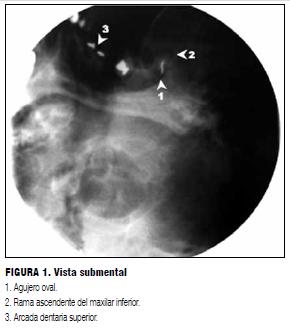

Se realizó fluoroscopía con enfoques anteroposterior, submental ligeramente lateralizado a izquierda (como se ve en la figura 1) y lateral (como se ve en la figura 2).

Una vez que la aguja se introdujo en el agujero oval (figura 1) se confirmó por vista lateral la dirección hacia el ángulo formado por el clivus y la aparte petrosa del temporal (figura 2).